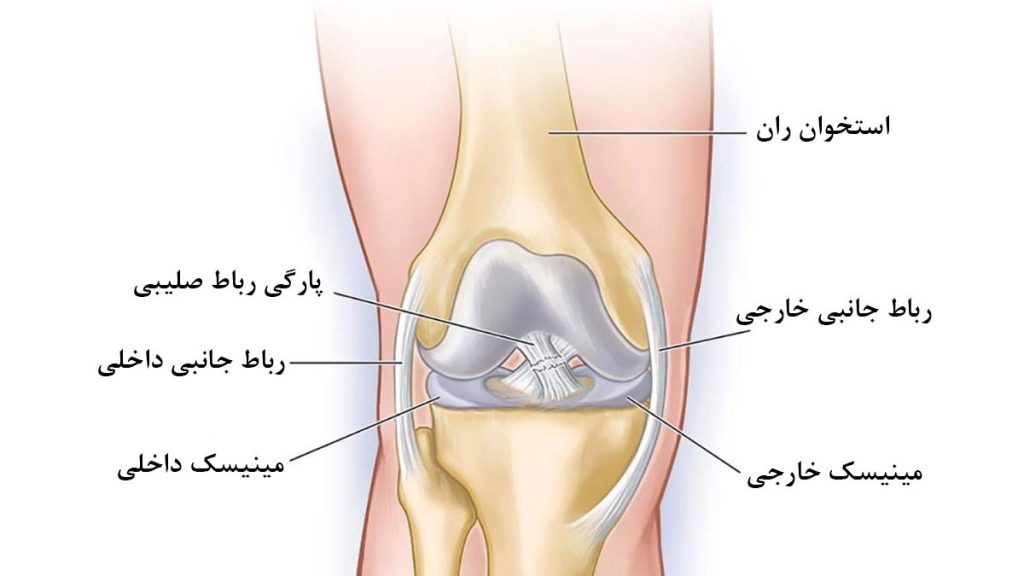

تست پارگی رباط صلیبی یکی از روشهای کلیدی برای تشخیص آسیبهای زانو بهویژه در ورزشکاران و افرادی است که دچار پیچخوردگی یا ضربه شدید به مفصل زانو شدهاند. رباط صلیبی جلویی (ACL) و رباط صلیبی خلفی (PCL) نقش مهمی در پایداری و حرکت طبیعی زانو دارند. در صورت آسیبدیدگی این رباطها، فرد دچار درد، تورم، ناپایداری و کاهش توان حرکتی میشود.

تست پارگی رباط جانبی زانو

تست پارگی رباط جانبی زانو یکی از مهمترین روشهای تشخیصی برای بررسی آسیبهای وارد شده به رباطهای داخلی (MCL) و خارجی (LCL) زانو است. این رباطها وظیفه پایداری جانبی زانو را بر عهده دارند و در اثر ضربه مستقیم، پیچش ناگهانی یا حرکات ورزشی سنگین دچار کشیدگی یا پارگی میشوند.

علائم پارگی مینیسک زانو

علائم پارگی مینیسک زانو معمولاً به تدریج یا ناگهانی پس از یک حرکت پیچشی یا ضربه مستقیم بروز میکنند. مینیسک نقش ضربهگیر و تثبیتکننده مفصل زانو را دارد و آسیب آن میتواند باعث اختلال در عملکرد طبیعی زانو شود. همچنین تورم، محدودیت حرکتی و گاهی قفل شدن زانو از نشانههای رایج این آسیب هستند. تشخیص دقیق نیازمند معاینه پزشک و در برخی موارد MRI است.

علائم پارگی رباط صلیبی و مینیسک

زمانی که پارگی رباط صلیبی با آسیب به مینیسک همراه باشد، شدت علائم بیشتر میشود. علائم پارگی رباط زانو در این شرایط شامل درد شدید، تورم سریع، احساس قفل شدن یا گیر کردن زانو، و صدای “پاپ” هنگام آسیب است. آسیب به مینیسک میتواند باعث شود که بیمار نتواند پای خود را کامل خم یا صاف کند. همچنین، درد در ناحیه داخلی یا خارجی زانو که با چرخش پا بدتر میشود، میتواند نشاندهنده آسیب به مینیسک باشد.

علائم پارگی داخلی رباط زانو

رباط داخلی زانو یا MCL یکی از رباطهای اصلی است که ثبات داخلی زانو را حفظ میکند. پارگی این رباط معمولاً در اثر ضربه به قسمت خارجی زانو رخ میدهد. علائم پارگی رباط زانو از نوع داخلی شامل درد در سمت داخلی زانو، تورم در همان ناحیه، حساسیت به لمس و ناتوانی در خم کردن کامل زانو است. در موارد شدید، بیمار ممکن است احساس ناپایداری هنگام ایستادن یا راه رفتن داشته باشد. در موارد خفیفتر، ممکن است تنها درد و التهاب بدون ناپایداری مشاهده شود که این مورد در نوع خودش از علائم پارگی رباط زانو میتواند باشد.